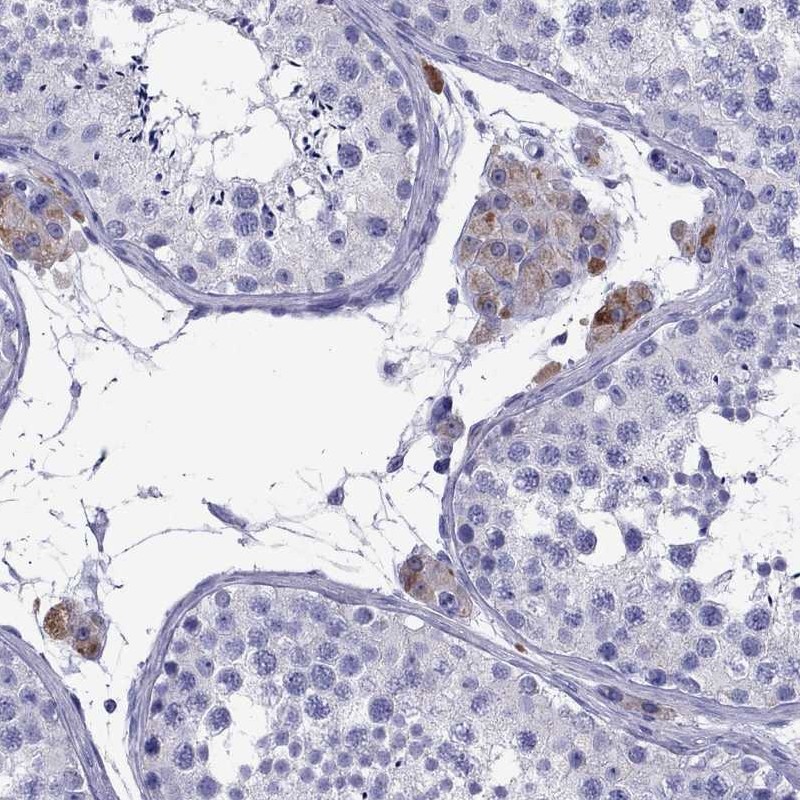

Immunohistochemistry analysis in human testis and endometrium tissues using Anti-TTLL13P antibody. Corresponding TTLL13P RNA-seq data are presented for the same tissues.